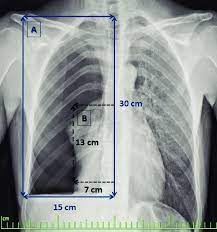

Pneumothorax / Case Report Covid 19 Associated Bilateral Spontaneous Pneumothorax A Literature Review In The American Journal Of Tropical Medicine And Hygiene Volume 103 Issue 3 2020 / Tension pneumothorax most commonly occurs in people with penetrating chest injuries.. This may be caused by physical trauma to the lung, such as a wound. Pneumothorax nursing interventions, treatment, pathophysiology nclex review for the different types of pneumothorax: There are several variations of pneumothorax. Pneumothorax is the medical term for a collapsed lung, a condition in which air or gas is trapped in the space surrounding the lungs causing the lungs to collapse. Also known as pneumothorax, collapsed lung is a rare condition that may cause chest pain and make it hard to breathe.

This is termed spontaneous pneumothorax. Pneumothoraces can be even further classified as simple, tension, or open. Pneumothorax nursing interventions, treatment, pathophysiology nclex review for the different types of pneumothorax: Pneumothorax, also called a collapsed lung, is when air gets between one of your lungs and the wall of your chest. It is reasonably common and has many different causes.

Scielo Brasil Pneumothorax As A Late Complication Of Covid 19 Pneumothorax As A Late Complication Of Covid 19 from minio.scielo.br In tension pneumothorax, patients are distressed with rapid laboured respirations, cyanosis, profuse diaphoresis, and tachycardia. The definition of a pneumothorax is an accumulation of air outside the lungs, but inside the chest wall. Tension pneumothorax most commonly occurs in people with penetrating chest injuries. In a healthy body, the lungs are touching the walls of the chest. Patients with a pneumothorax typically report dyspnoea and chest pain. A pneumothorax occurs when air leaks into the space between the lung and chest wall (called the pleural space). A small pneumothorax may cause few or no symptoms. Pneumothorax occurs when air enters the space around your lungs (the pleural space).

Other signals that the problem may be a collapsed lung are: Normally, the outer surface of the lung sits next to the inner surface of the chest wall. The lung and the chest wall are covered by thin membranes called pleura. It occurs when air accumulates between the parietal and visceral pleura inside the chest. Pneumothoraces can be even further classified as simple, tension, or open. A pneumothorax is an abnormal collection of air in the pleural space between the lung and the chest wall. Pneumothorax is defined as the presence of air or gas in the pleural cavity (ie, the potential space between the visceral and parietal pleura of the lung), which can impair oxygenation and/or. A pneumothorax occurs when air leaks into the space between your lung and chest wall. The pressure causes the lung to give way, at least partly. Pneumothorax is classified as spontaneous or traumatic. Hemothorax occurs when there is blood in that. This air pushes on the lung, which makes it collapse. The air accumulation can apply pressure on the lung and make it collapse.

Patients with a pneumothorax typically report dyspnoea and chest pain. Pneumothoraces can be even further classified as simple, tension, or open. Pneumothorax is defined as the presence of air or gas in the pleural cavity (ie, the potential space between the visceral and parietal pleura of the lung), which can impair oxygenation and/or. In a healthy body, the lungs are touching the walls of the chest. The definition of a pneumothorax is an accumulation of air outside the lungs, but inside the chest wall. It is reasonably common and has many different causes. A pneumothorax is a collection of air outside the lung but within the pleural cavity. A pneumothorax can be a complete lung collapse or a collapse of only a portion of the lung. A pneumothorax occurs when air leaks into the space between the lung and chest wall (called the pleural space). This air pushes on the lung, which makes it collapse. Also known as pneumothorax, collapsed lung is a rare condition that may cause chest pain and make it hard to breathe. A large pneumothorax can squash the lung and cause it to collapse. This is termed spontaneous pneumothorax.